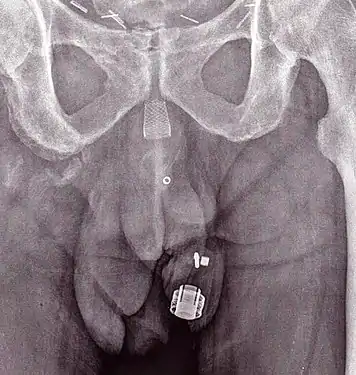

Рентгеновское изображение имплантированного ZSI 375. Устройство деактивировано — пружина сжимается ниже верхушки цилиндра. У пациента недержание мочи.

Рентгеновское изображение имплантированного ZSI 375. Устройство активировано — пружина разжимается в верхней части цилиндра. Пациент сдерживает мочу.